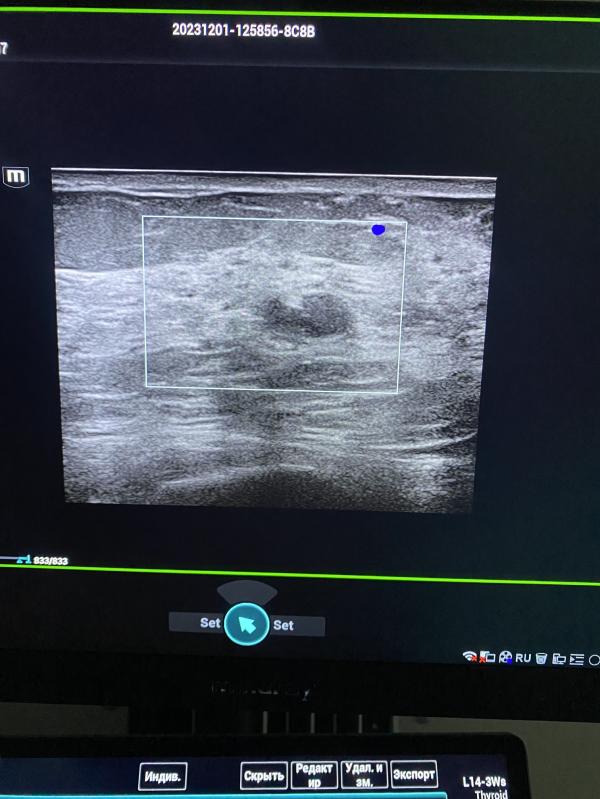

Нужно ли делать УЗИ молочных желез, если обнаружили патологию? Консультация маммолога и дообследование

post image 1

Выявлены патологические участки в правой молочной железы. Пациентка отправлена на дообследование к маммологу.